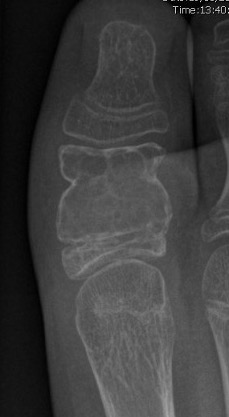

X-ray

Eccentric, sharply demarcated lytic lesion

- no sclerosis around lesion

- narrow zone of transition

- metaphysis, extending into epiphysis

- no mineralization

Distal Radius

Abuhejleh et al Eur J Orthop Traumatol Surg 2020

- 57 patients with GCT's of distal radius

- 29% (10/34) recurrence with intra-lesional treatement but no complications

- 4% (1/23) recurrence with wide resection / arthrodesis but 30% complication rate

- increased risk recurrence for Grade 3

- wide resection / arthrodesis should be reserved for grade 3